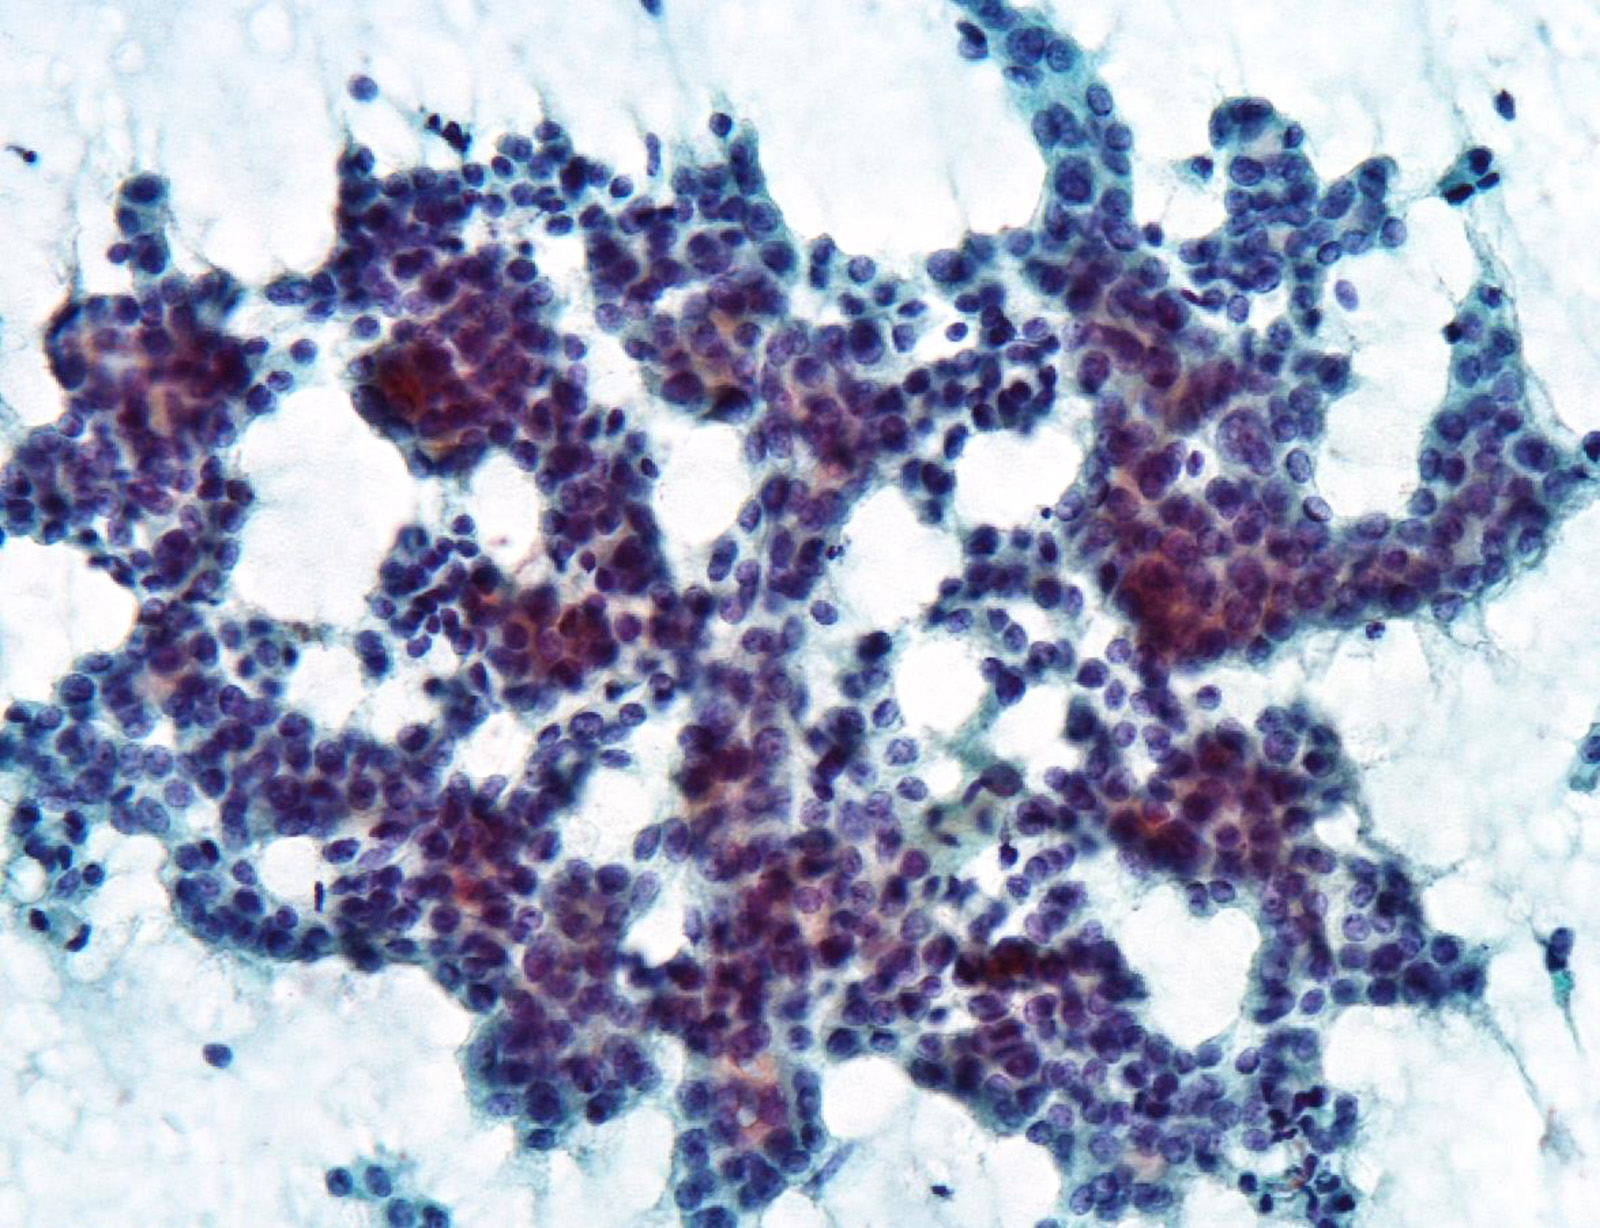

Cytology description

- Hypercellularity

- Small, round and dense colloid (hyaline colloid) may be present, sometimes within follicles

- Cells arranged in microfollicles or trabecular pattern

- Nuclear enlargement but may lack prominent nuclear features of papillary carcinoma (Am J Clin Pathol 1999;111:216)

- Highly suggestive of syncytial clusters, microfollicular architecture, chromatin clearing and nuclear grooves (Acta Cytol 2006;50:663)

- Classified by Bethesda system as categories III to VI

- Cytologically unable to distinguish between noninvasive and invasive

Cytology images

Contributed by Ayana Suzuki, C. T.